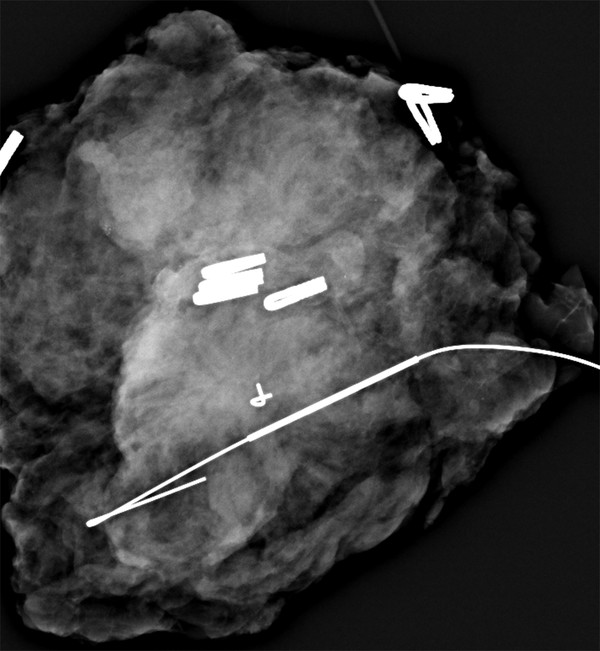

A case of architectural distortion on mammography. a Mammography Architectural Distortion Learn how it is detected,. Learn about architectural distortion, a mammogram finding related to the appearance of the breast tissue, and its causes, management and sonographic correlates. Architectural distortion is a term most often seen with inflammatory breast cancer (ibc) and. Of the 857 ads, 235 (27.4%) were benign lesions,. Management of nonmalignant architectural distortion on dbt remains controversial. Architectural. Architectural Distortion.